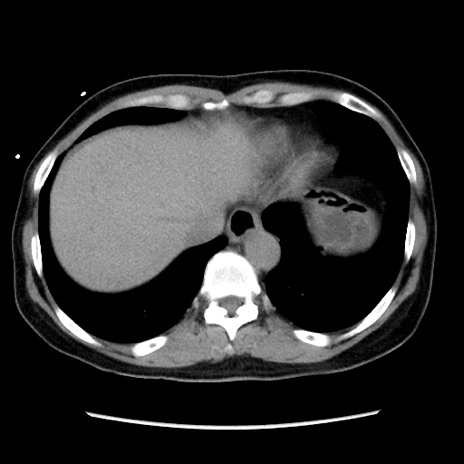

冠状断像

【症例】 50歳代女性

【主訴】 腹痛

【現病歴】前日生レバーを食べた。今朝に排便あり。 昼前に突然発症の腹痛を生じ、当院救急外来を受診した。

【既往歴】 子宮筋腫にてで子宮全摘後

【身体所見】 意識清明、腹部:平坦、軟、下腹部やや左を中心に圧痛・反跳痛あり、筋性防御あり

【データ】WBC 7800、CRP 0.07